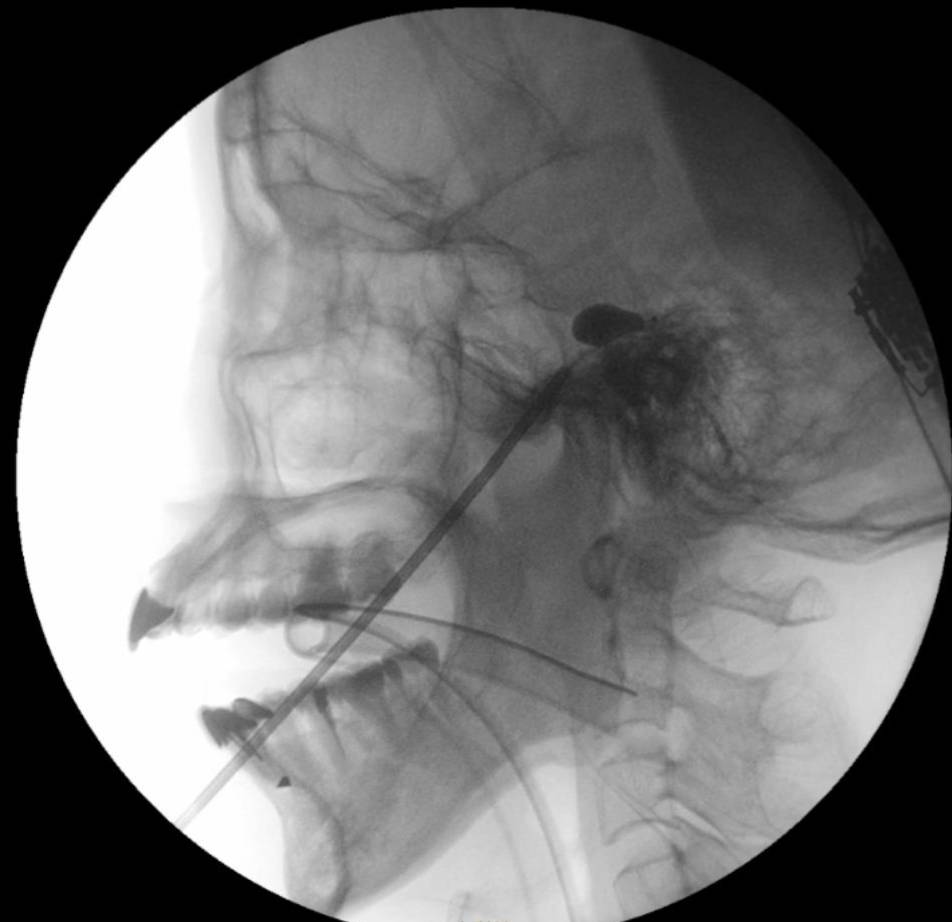

經皮球囊壓迫術屬微創介入治療,主要針對與三叉神經相關的疼痛。手術期間,醫生會經面頰穿刺,將微型球囊導管置入顱底的三叉神經節,並注入顯影劑擴張球囊,藉此壓迫負責傳遞痛覺的神經纖維,以阻斷疼痛訊號。過程中會透過即時透視影像,確認球囊呈現梨形,以確保位置準確。

瑪麗醫院麻醉、疼痛和圍術期醫學顧問醫生陳智榮醫生指出,傳統射頻消融術(RFA)需患者在清醒狀態下配合感覺測試,以協助定位疼痛來源;相比之下,經皮球囊壓迫術可在全身麻醉下完成,病人毋須承受手術期間的不適,整體治療體驗較佳。他亦指出,該技術一次治療可同時覆蓋三叉神經三個主要分支,適用範圍較廣。